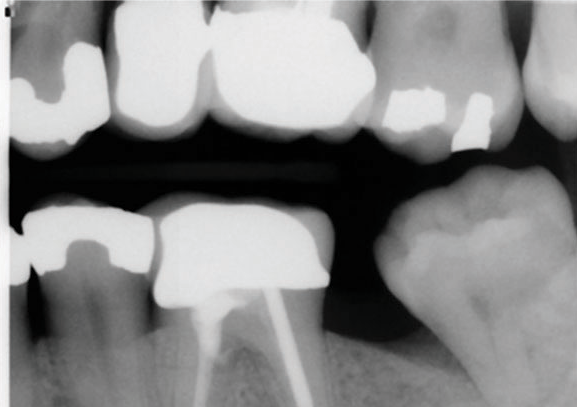

(5.) Preoperative radiograph of tooth No. 19 following a pulpectomy procedure that was complicated by an intraoperative furcal perforation.

Figure 5

(6.) Postoperative radiograph showing immediate perforation repair using MTA followed by complete obturation.

Figure 6